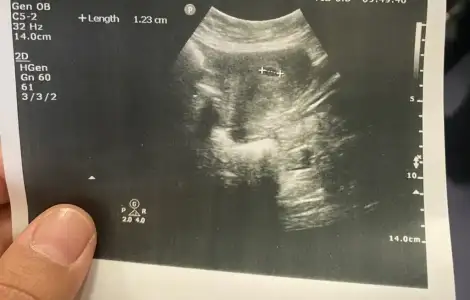

Selam kızlar bakalım ne tutturmuşum iki kızdan sonra 6 haftalığız henüz

• IMG_6683.webp

IMG_6683.webp

32,2 KB · Görüntüleme: 124